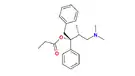

Several semi-synthetic opioids were developed in Germany in the 1910s. The first, oxymorphone, was synthesized from thebaine, an opioid alkaloid in opium poppies, in 1914.[228] Next, Martin Freund and Edmund Speyer developed oxycodone, also from thebaine, at the University of Frankfurt in 1916.[229] In 1920, hydrocodone was prepared by Carl Mannich and Helene Löwenheim, deriving it from codeine. In 1924, hydromorphone was synthesized by adding hydrogen to morphine. Etorphine was synthesized in 1960, from the oripavine in opium poppy straw. Buprenorphine was discovered in 1972.[228]

- Semi-synthetic opioids: created from either the natural opiates or morphine esters, such as hydromorphone, hydrocodone, oxycodone, oxymorphone, ethylmorphine and buprenorphine;